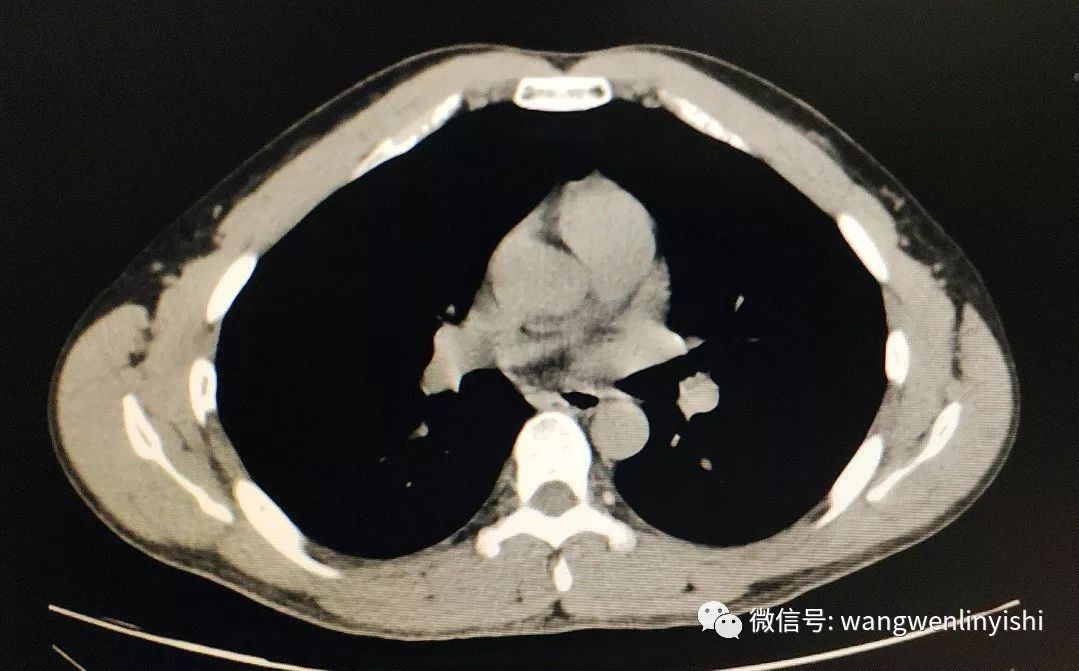

入院查体,前胸壁明显畸形,上半胸壁前突,以正中最明显,突起向下延伸,两侧胸壁下缘呈弧形下垂,正中凹陷。凹陷底部可见心脏搏动。双肺呼吸音清晰,未闻及啰音。心率较快,90次/分,未闻及杂音。X线检查提示前胸壁上半突起,下半局部凹陷。CT提示前胸壁前突。

(前胸壁明显畸形。)

(前胸壁呈典型Wenlin胸改变。)

(前胸壁下方凹陷。)

(前胸壁上部明显前突。)